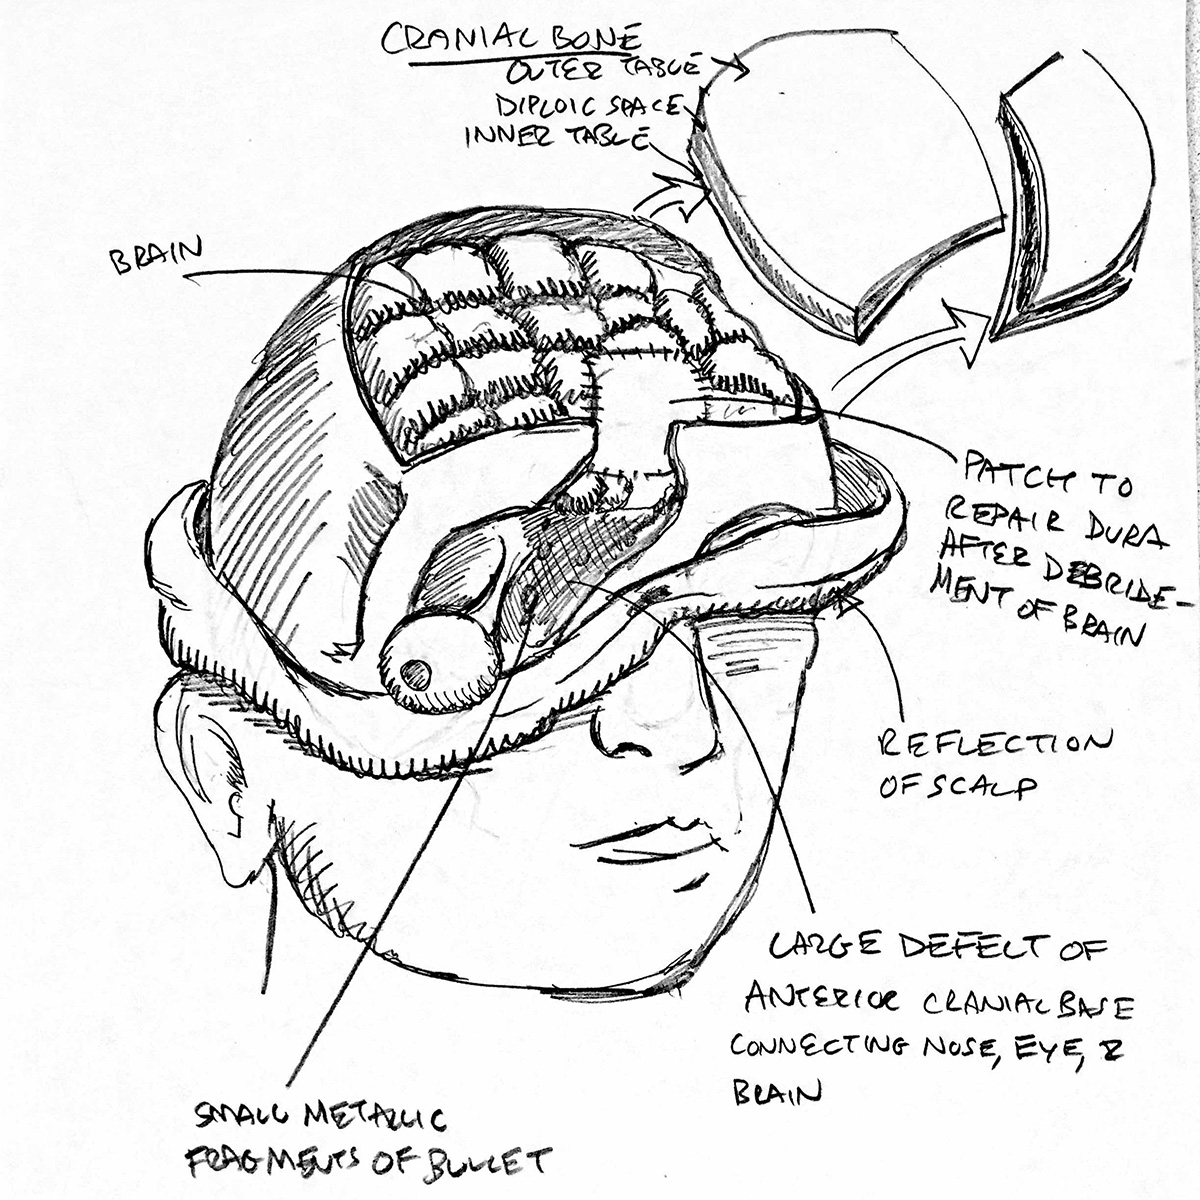

Gunshot Wounds Illustrations, Royalty-Free Vector Graphics & Clip Art …

Gunshot Wounds Illustrations, Royalty-Free Vector Graphics & Clip Art …